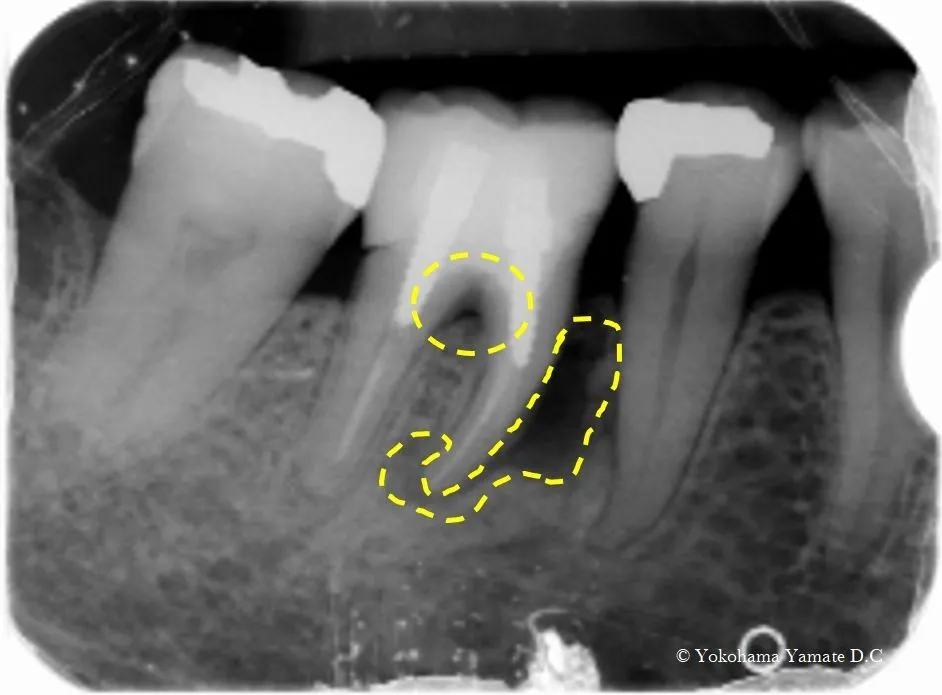

咬むと痛い歯肉に、おできがある舌側近心6mm骨吸収有ゾンデを入れてみた所骨がそこまで下がっていた。

歯周病原菌による感染層までゾンデを入れてレントゲン写真を撮る

術後6ヶ月での骨様組織の改善状態